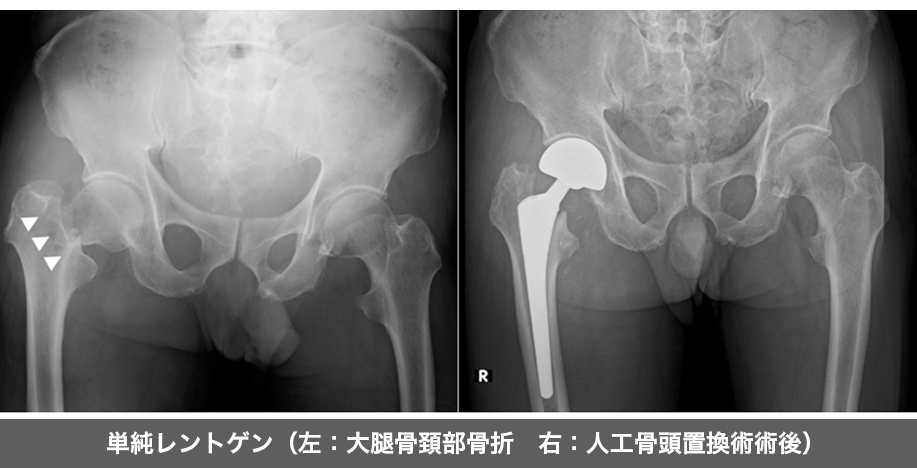

大腿骨には頚部と転子部があり(右図参照)、骨折してしまう場所によって手術方法が変わります。

大腿骨頚部骨折は癒合しにくい骨折であり、体重をかけて歩けるようになるためには手術が不可欠となります。

骨折した骨頭の変位の仕方によって以下の手術方法の選択肢があります。

①人工骨頭置換術

骨頭を切除し、人工骨頭に置き換える手術です。

関節の状態など考慮し人工股関節全置換術を選択することもあります。